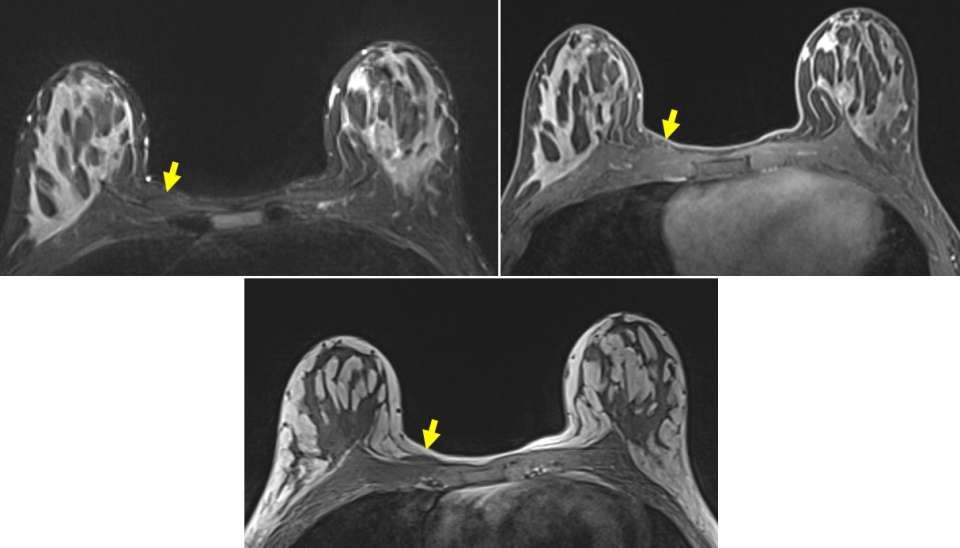

Magnetic Resonance Imaging and Computed Tomography Appearance

On MRI, the sternalis muscle demonstrates signal isointense to skeletal muscle. Likewise, CT scans depict the sternalis muscle as a well-demarcated structure with attenuation values similar to those of muscle, located anterior to the sternum. The shape is most often flat but can also be oblique or irregular (4). The presence of enhancing components on either MRI or CT is not typical and should prompt further evaluation or tissue sampling.